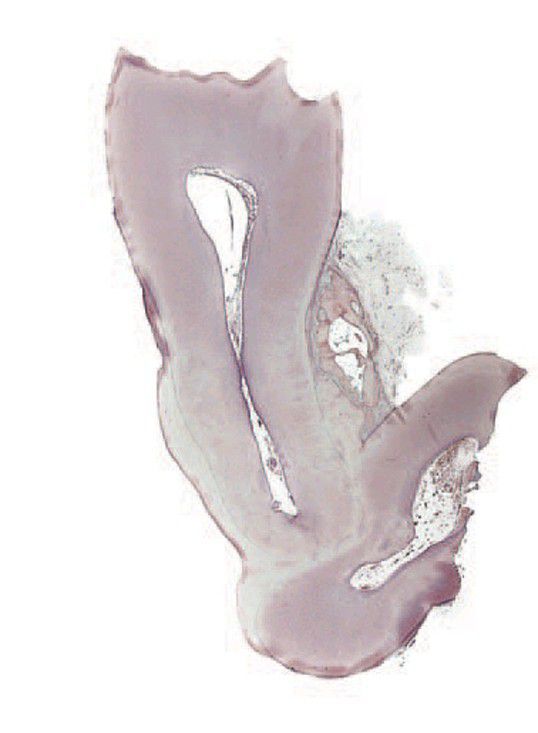

Concrescence

. Histological section of fused teeth reveals that the teeth are joined by cementum and not dentine